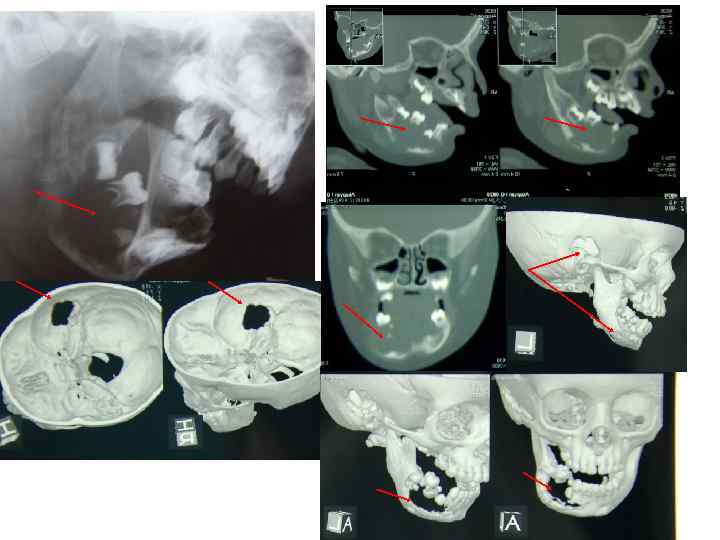

• 1. Рентгенологическое исследование. Исходные данные получают при обычной рентгенографии в нескольких проекциях. Она позволяет определить локализацию, форму, размеры опухолевого очага, степень деструкции костной ткани, наличие патологического перелома. При некоторых видах опухолей эффективна контрастная рентгенография.

• Компьютерная томография Рентгеновские лучи после прохождения через тело больного воспринимаются детекторами и преобразуются в электрические сигналы, которые поступают в компьютер, где и преобразуются в изображение органов и тканей.

Компьютерная томография имеет следующие преимущества перед обычной рентгенографией: • 1. Возможность получения изображения всех видов тканей (костной, хрящевой, мышечной, жировой и т. д. ); • 2. Позволяет увидеть изображение не только исследуемого органа, но и других органов и тканей, находящихся на данном уровне ("срезе"), определить их форму, величину, топограф-анатомические взаимоотношения; • 3. Можно сложить изображение поперечных срезов и получить продольное изображение органов; • 4. Даёт возможность увеличения в несколько раз патологического очага и проведения точных измерений исследуемой области; • 5. Даёт чёткое изображение тканей при различии их плотности в 15— 20%, тогда как обычная рентгенография — при разнице плотностей, не превышающей 0, 5%; • 6. Позволяет судить об эффективности лечения; • 7. Помогает получить изображение опухоли, размеры которой не превышают несколько миллиметров (не исключены ложноположительные результаты).